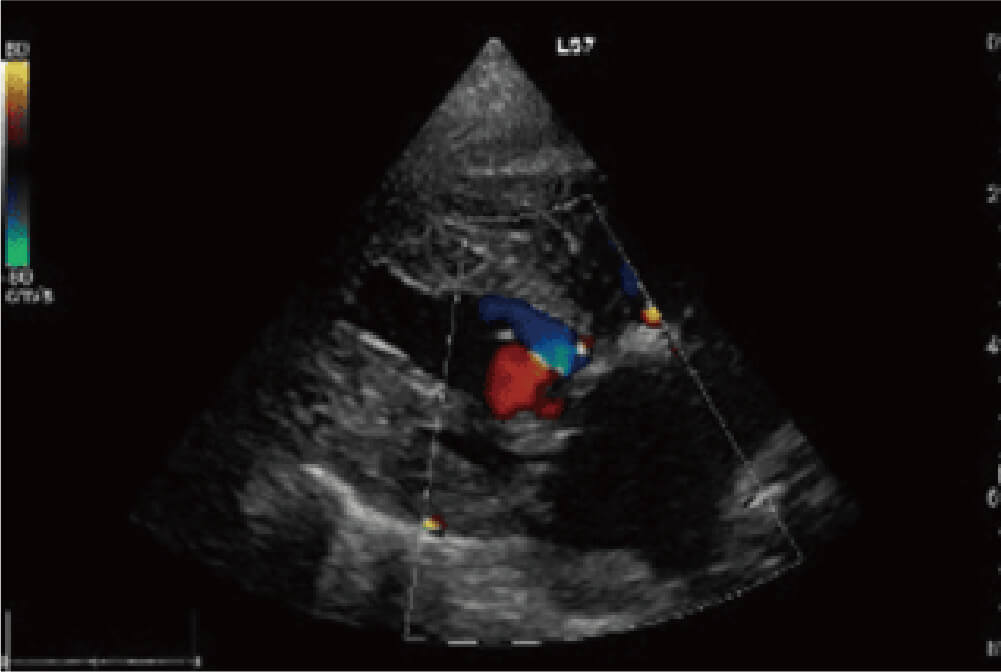

右図は僧帽弁形成術術後の画像で弁尖の位置が正常化し,前尖・後尖の良好な接合が得られたことで逆流が消失しています。